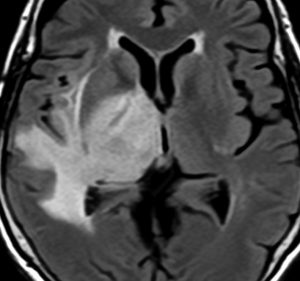

典型的な膠芽腫のガドリニウム増強画像です。右の側頭葉から発生したために目立った症状が無く,この大きさで発症しました。何となくボッとしていると言うのが訴えでした。腫瘍の周囲がガドリニウムで白く増強されて,内部は壊死で低信号(黒っぽい)になっています。

左がガドリニウム増強像で,手術ではこの部分が取れれば全摘出といわれるのですが,実際は右側のフレア画像で白っぽく見える所には腫瘍が滲み込んでいます。この部分を全て摘出してはじめて,画像上の全摘出といいます。全摘出は無理でしょう